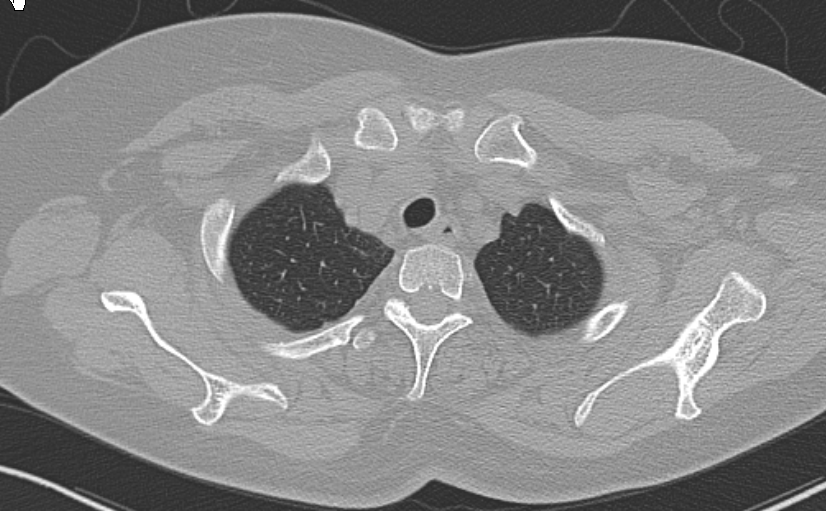

肺窗薄层1.5mm

A